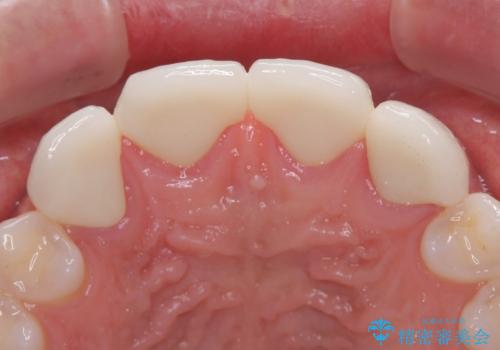

欠損して隙間のある前歯 オールセラミッククラウンで自然な口元に

ひとつひとつの歯の幅は非常に大きくなりましたが、手っ取り早く隙間が改善されたとのことで、大変満足していらっしゃいました。